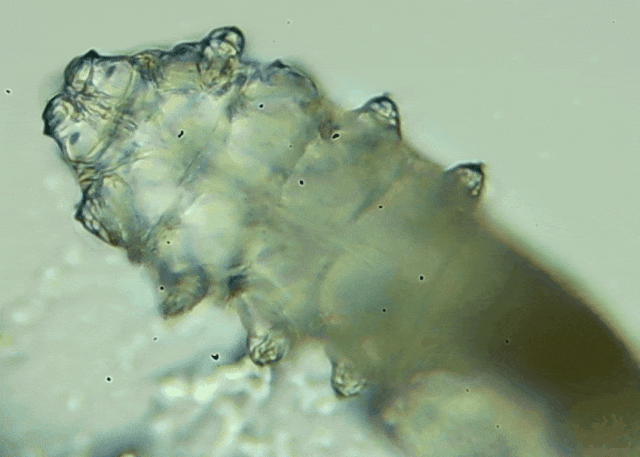

我只是眼睛癢,結(jié)果醫(yī)生說我睫毛里有80只蟲?這不是恐怖片,而是真實(shí)的病例:武漢一13歲男孩,右眼9根睫毛里檢出39只螨...[詳細(xì)]